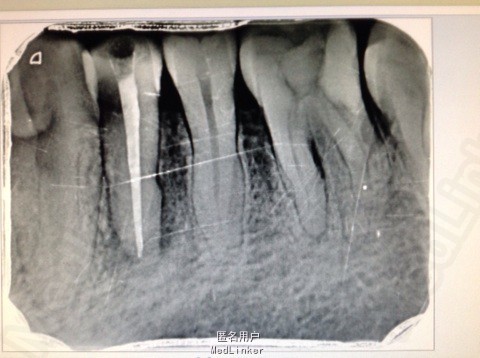

主诉:患者左下后牙胀痛数日。 病史:数日来,患者左下后牙食物嵌塞,近日疼痛不适影响进食,来院就诊。

查体:34牙合面无龋坏,探(-),冷热诊疼痛不明显,叩(+),颊侧可以可以看到窦道,X线示近中龋坏龋坏深达牙髓腔。远中及根尖有透色区。

诊断:34根尖周炎 治疗: 局麻下34去腐,开髓揭髓顶降牙合,冲洗髓腔,拔髓疏通根管,测量根管镍钛器械进行根管预备,低浓度次氯酸钠进行根管的冲洗化学预备,吸潮纸尖拭干根管,氢氧化钙进行诊间根管封药,对牙周进行洁治刮治,患者观察一周复诊,窦道明显的闭合,患者无不适感叩(-),去除暂封物进行根管试尖,X线示恰充,进行热牙胶垂直加压连续波充填法进行根管充填。暂封观察进行嵌体修复。